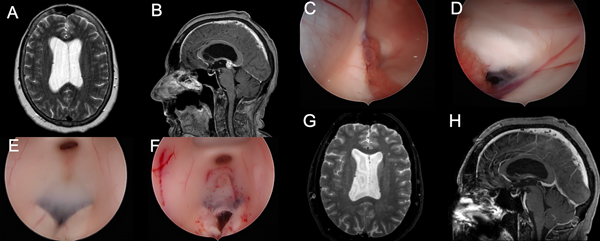

Se presentan en figuras 8 a 12 los casos ilustrativos más representativos de nuestra serie.

Figura 9: Hidrocefalia en contexto de subestenosis acueductal por metástasis de cáncer de mama: A-B) RM preoperatoria. C-F) Hallazgos intra-operatorios, nótese la hidro disección del foramen de Monro cerrado. G-H) RM cerebral postoperatoria.